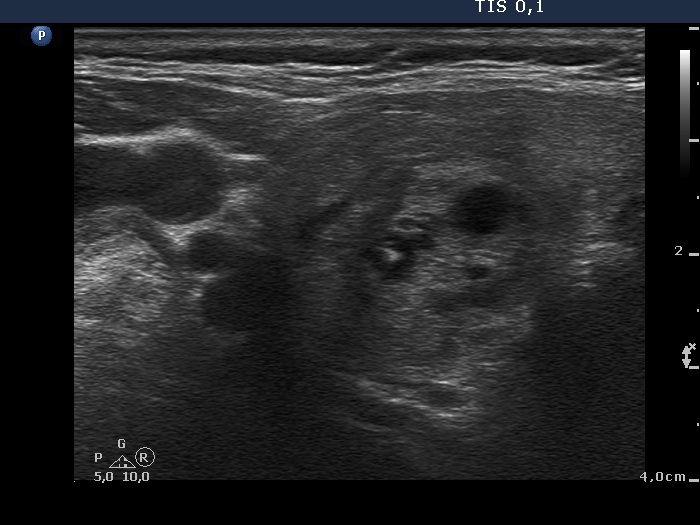

Clinical presentation: A 77-year-old woman was referred for evaluation of a nodular goiter which has been known for years. A mass was found in the left upper mediastinum on CT scan 6 weeks ago on evaluation of pneumonia. The patient had no neck complaints.

Ultrasonography. The thyroid was enlarged and had numerous nodules of different echogenicities. From an oncological point-of-view, the nodule located in the isthmic part of the left lobe was the most important. The lower pole of both lobes could be visualized on ultrasound examination.

Aspiration cytology of the nodule in the isthmic part of the left lobe resulted in benign cystic-colloid goiter.